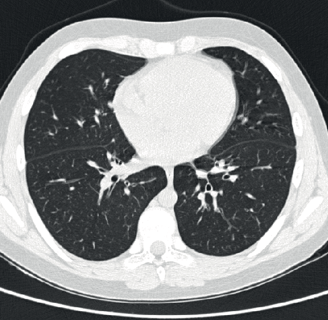

India Imaging is the first to introduce 96 Slice CT scanner. The advanced scanning technologies, combined with our CT specialist, are able to provide the highest level of accuracy for diagnosing all types of illnesses in the body. These equipment are capable of performing cutting-edge tests like Pulmonary Angiograms, Brain Angiograms, True-match imaging, etc.

We are the first to introduce 96 Slice CT into the city. The state-of-the-art 96 slice CTs provide ultra-fast volume imaging. Further, all routine CT scans are done using ultra-thin slices with volume acquisition and isometric reconstruction that can be obtained in any plane. 3D-CT examinations are routinely performed along with a virtual colonoscopy, virtual bronchoscopy, and whole-body scanning. Patients pay the same charges for routine CT scans as they would at any other facility that does not have these high-quality machines.

This scanner has a special x-ray tube and rotation speed, making it capable of performing very rapid scanning. It is used for performing non-invasive CT angiograms of the heart, brain, and other blood vessels of the body. The 96 slice configuration also provides breakthrough performance in advanced pulmonary imaging, multi-organ trauma evaluation, and low-dose paediatric applications to boost clinical capabilities to the highest level attainable.

India Imaging's latest 96 Slice CT provides the benefits of high-resolution, low-dose scanning with increased integration and collaboration. It provides consistent image quality across a diverse patient population and a wide range of exam types, enabling healthcare organizations to increase their care capabilities to treat more patients.

This high-end CT enables us to do scans in one go of the neck, chest and abdomen. Also, we can do triple-phase studies of the abdomen with sub-millimetre scan thickness. This state-of-the-art CT machine is capable of doing high-resolution CT Angio of the abdomen down to the feet in one acquisition and at a lower contrast dose. Other applications include brain perfusion, lung nodule analysis, and vessel analysis, allowing you to care for a wide range of patients with ease and efficiency.